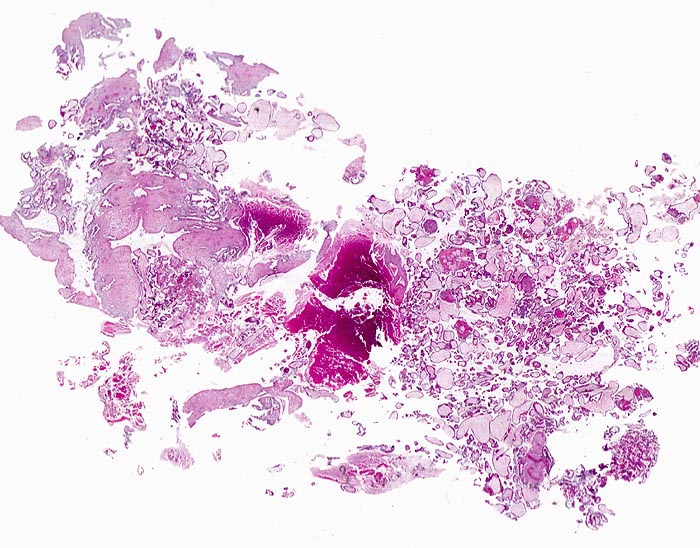

PathoPic ID 4671 - Abortkurettage

Abortkurettage

angeboren /genetisch/Missbildung

Abortmaterial

Paidopathologie

In der Übersicht sind

Deziduafragmente,

Blutkoagel,

Plazentarzotten und

Endometriumfragmente erkennbar. Anteile eines Embryo fehlen.

Missed abortion in der 11. Schwangerschaftswoche, sonographisch entsprechend der 9. Schwangerschaftswoche.